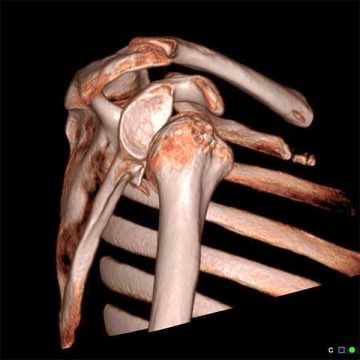

Datortomografiundersökning (DT): En datortomografiundersökning är en skiktröntgen som i detalj kan påvisa eventuella skador på ledhuvud eller ledskål. Dessa skador har betydelse för val av rätt behandling.